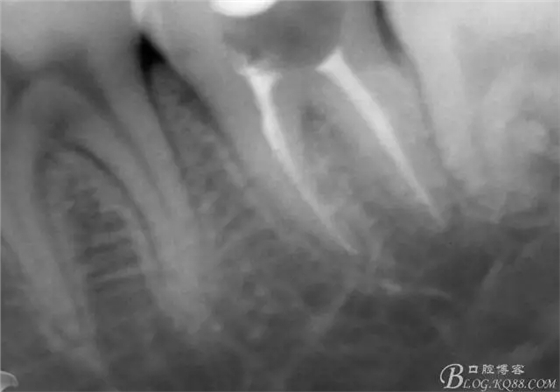

X線示牙膠尖到達(dá)工作長度,故行AH-PLUSH糊劑配合卡瓦熱牙膠機(jī)運(yùn)用連續(xù)波充法根充,暫封拍根尖片。

第四次復(fù)診,37叩(—)。此次行冠部修復(fù),因涉及38的拔除,患者不愿拔除,與患者介紹修復(fù)材料與方法,擬37E.max嵌體修復(fù),術(shù)前常規(guī)簽修復(fù)知情同意書。